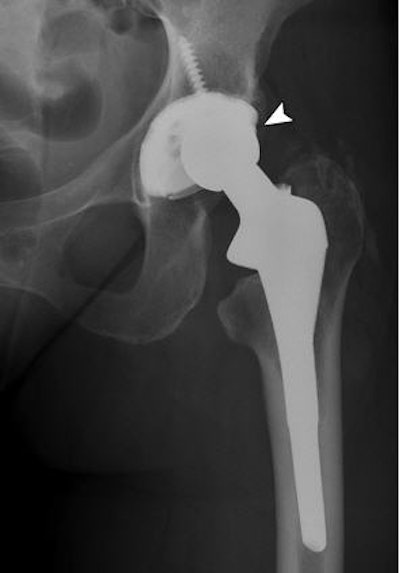

Frontal radiograph of pelvis shows disassociation of polyethylene liner from its acetabular cup (arrowhead) in total hip replacement in 65-year-old woman.

Finally, the investigators saw one disassociation of the polyethylene liner of a total hip replacement from its acetabular cup, as well as one inguinal hernia, one fracture of the proximal phalanx of the great toe, and two cases of solitary joint effusion.